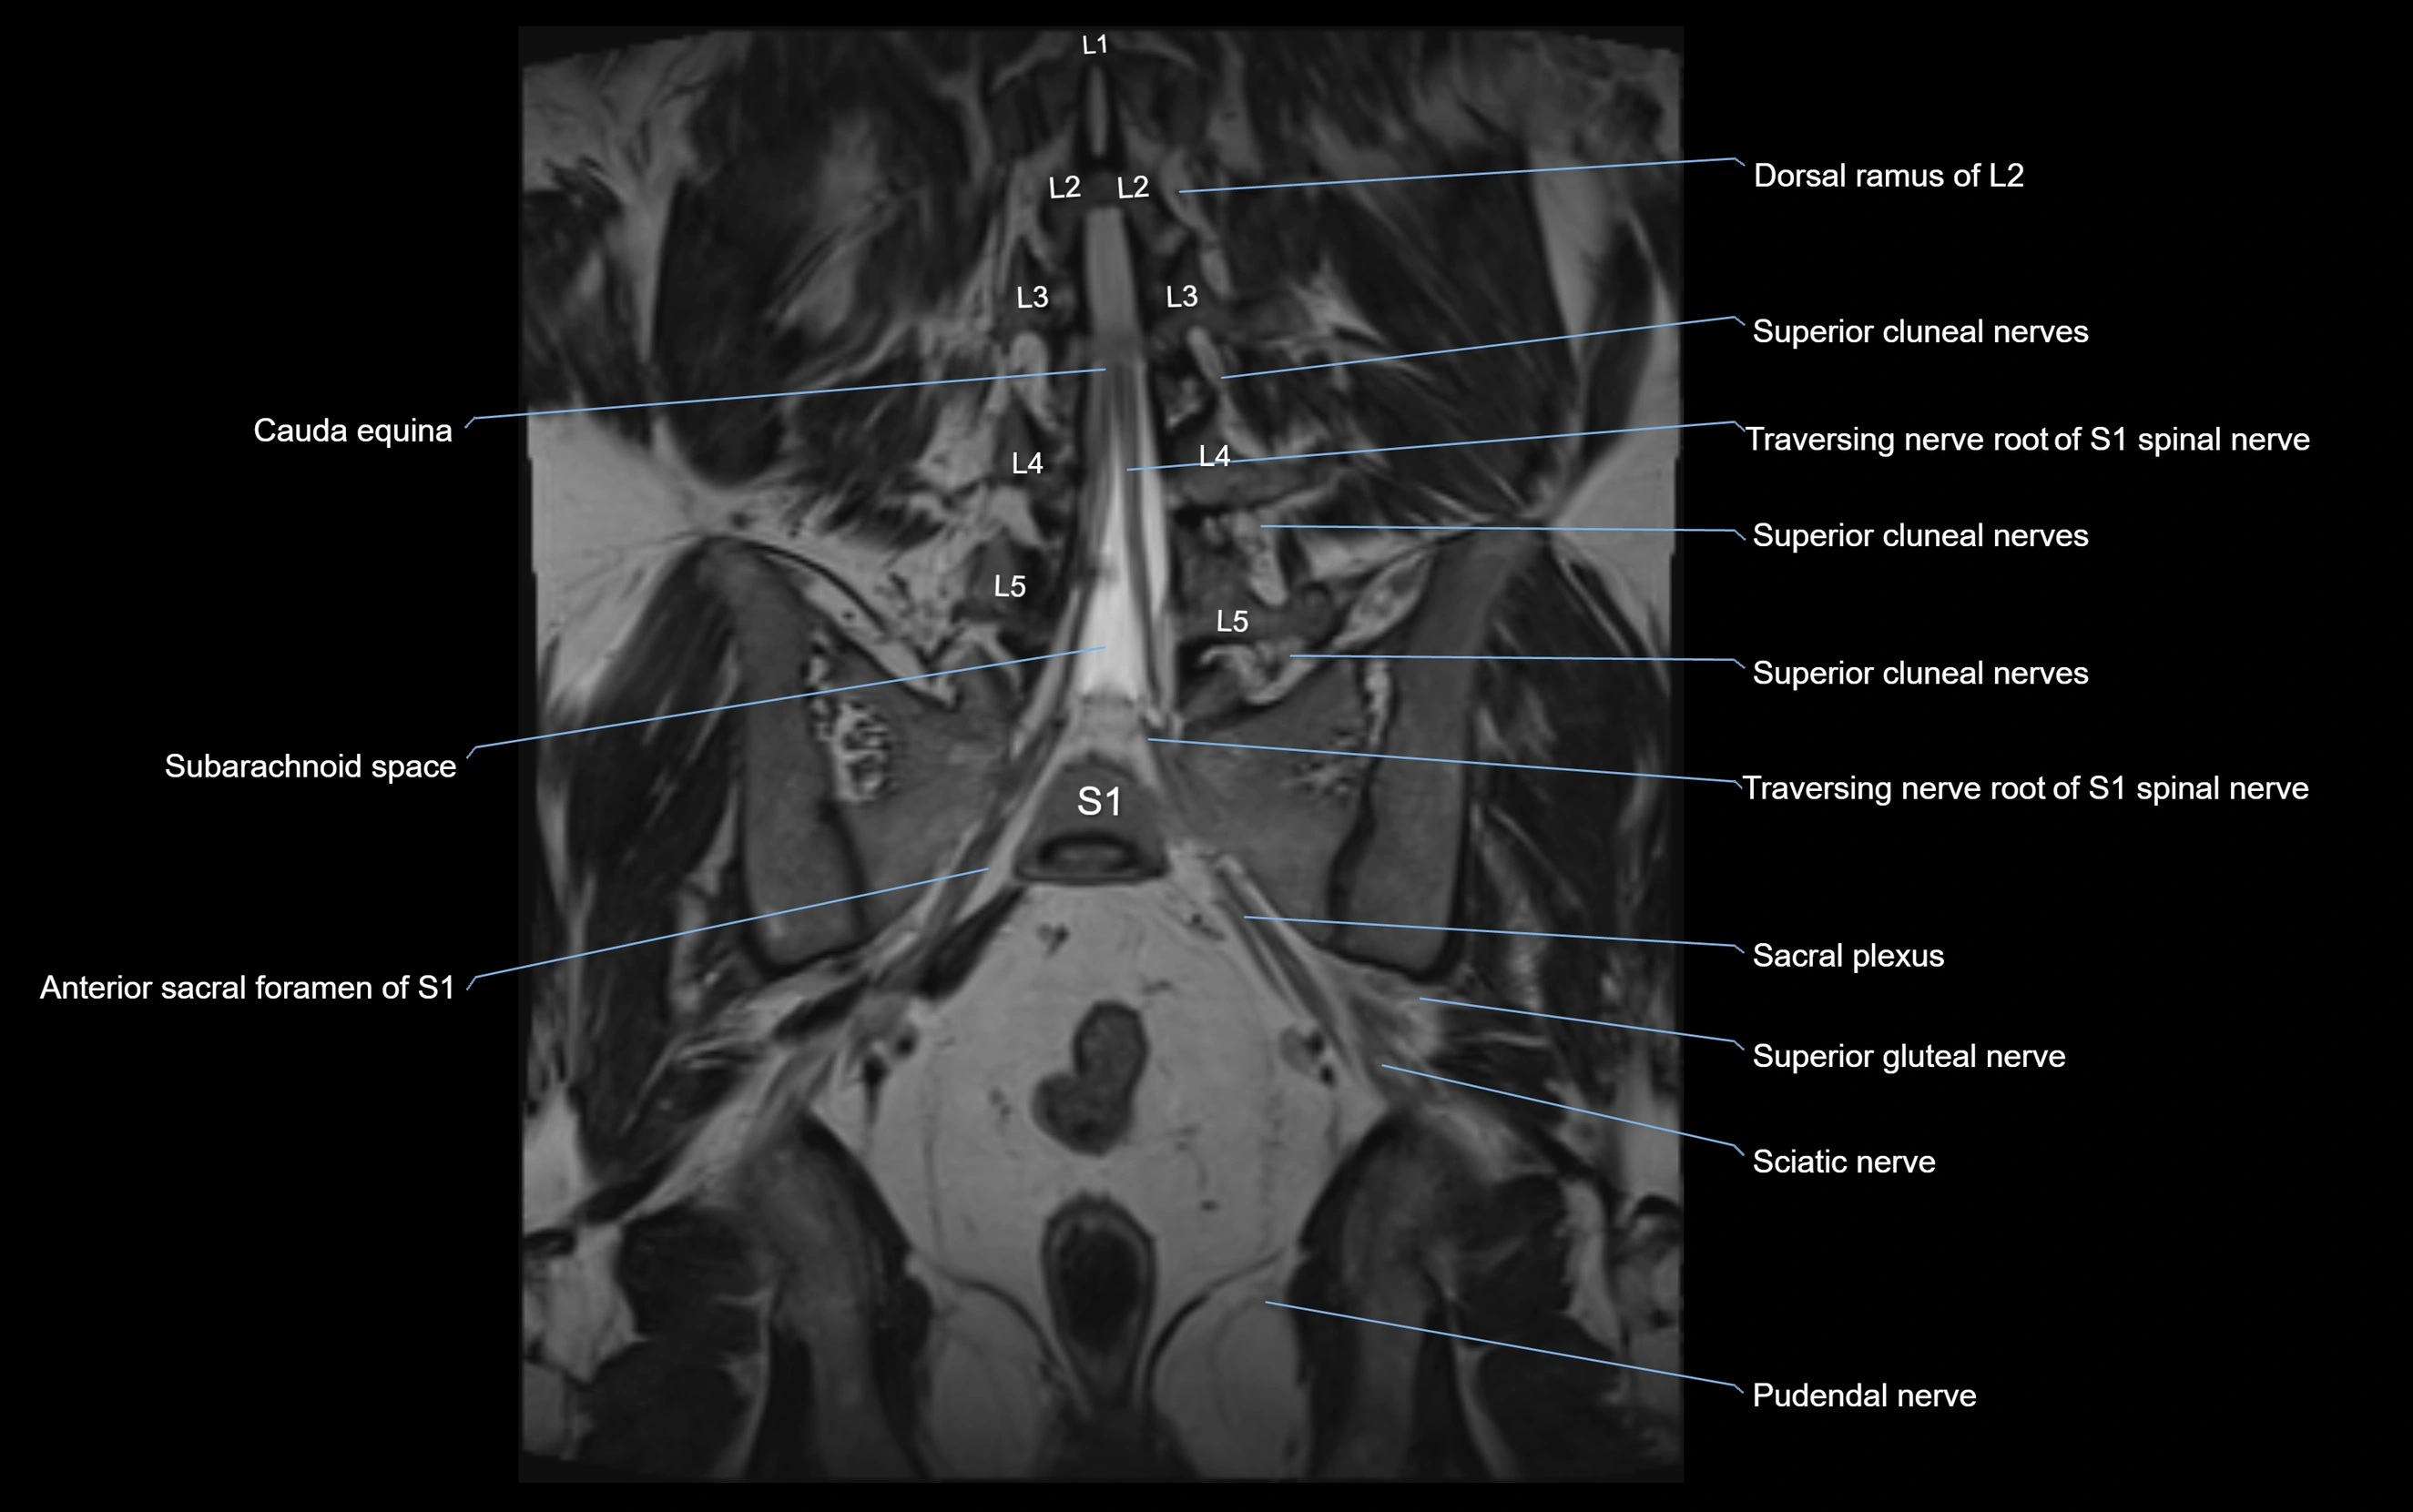

MRI image

image